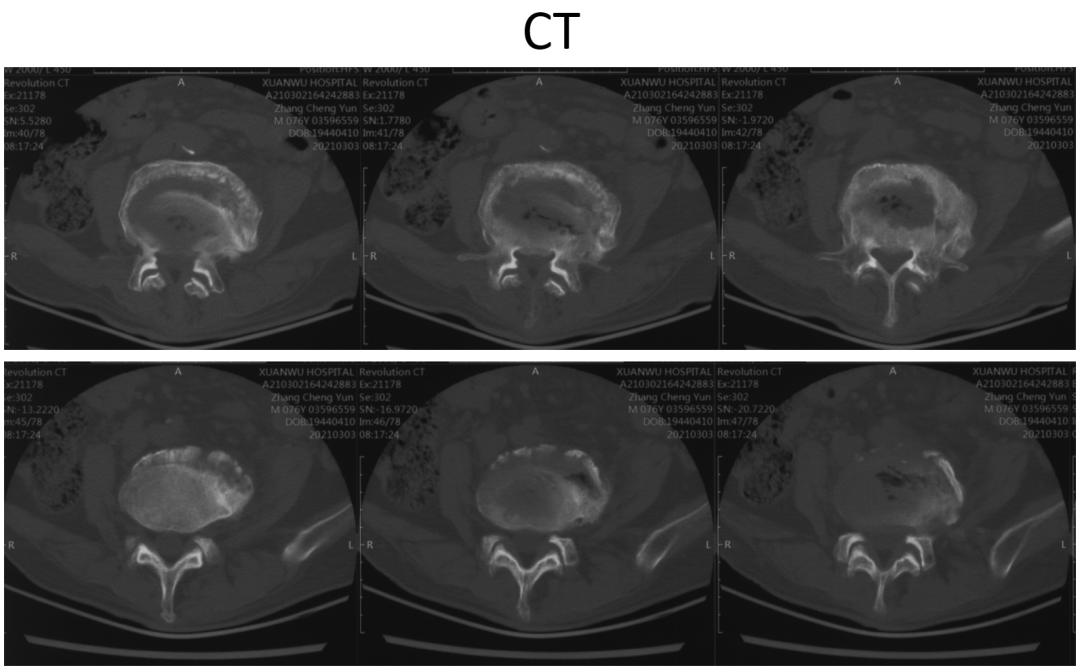

讨论主题:L4压缩骨折伴脊柱侧后凸畸形

影像资料:

腰椎侧后凸畸形

腰椎陈旧性压缩性骨折(L4)